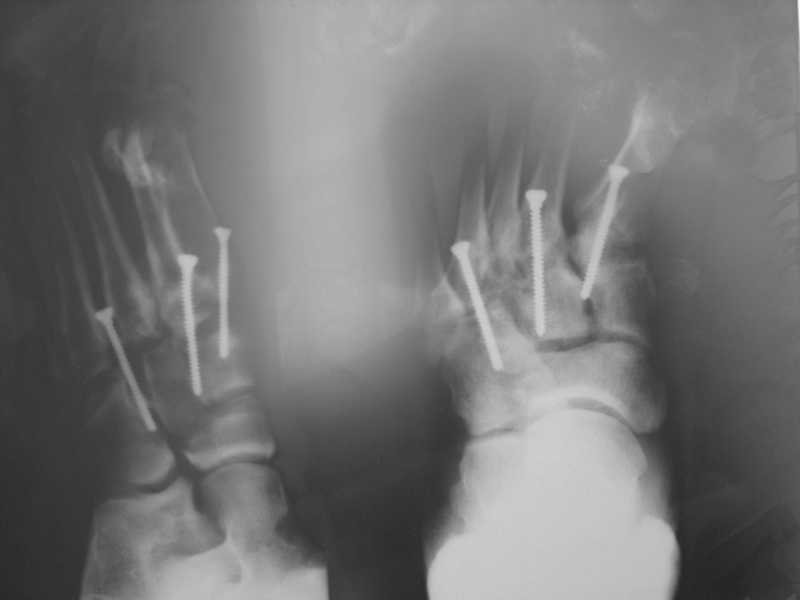

Здравствуйте , уважаемые коллеги. Обратился пациент, мужчина 42лет. для дальнейшего

лечения. Травма 11.09., ДТП.

15.09 проведено оперативное лечение (Блокирующий стержень левого

бедра - статическая система. Открытое вправление вывиха в суставе

Лисфранка и фиксация мет. фиксаторами.)

2. О суставе Лисфранка...

По суставу Лисфранка : 1- 8 -9 нед . полный покой в гипсовой шине,а

потом дозированная нагрузка. 2- Сейчас (на 7 нед.) пригипсовать

каблук под пятку и давать дозированную нагрузку, и на 12 нед,

Собственно такая фиксация сустава после вывизи никакой гипсовой иммбилизации не подразумевает! Через 6 недель винты можно удалять и разрешать полную нагрузку.... Прошло уже 7 недель, на сколько я понял, .....

Резюме: Удаляйте сейчас винты из стопы, динамизируйте стержень на бедре..Дайте нагрузку... Обсудите с больным вероятность и необходимость возможной реоперации на бедре, не дожидаясь таких осложнений как несращение, рефрактура и/или перелом штифта...

Как Вы считаете коллеги,насколько оптимальна одномоментная динамизация и удаление фиксаторов из сустава Лисфранка,а до этого времени разработка суставов?

Вы считаете что фиксаторы из Лисфранка стоит удалять по истечению 8-10 месяцев и не ранее?